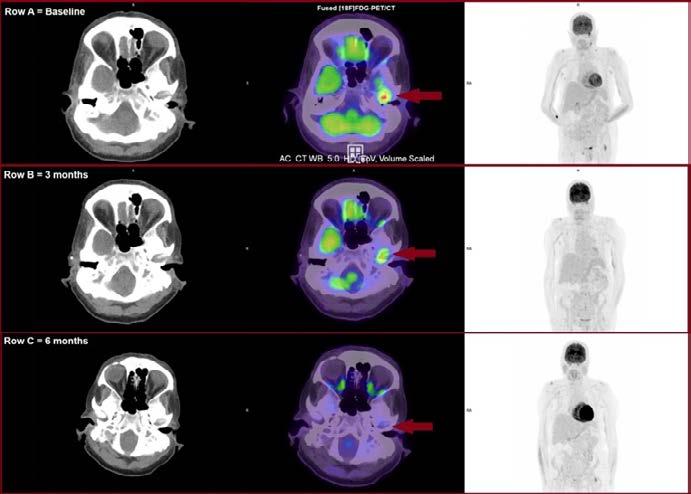

Due to inconclusive CT and MRI findings, further imaging was warranted. While 99mTc-HDP and 67Ga-Citrate scintigraphy may be used to investigate NOE, [18F]FDG-PET/ CT was selected due to increased access, reduced imaging time, quantitative capability, improved spatial resolution and anatomical localisation [3]. The patient fasted for four hours prior to the scan, and blood glucose levels measured 9.1mmol/L. The patient was administered 185.5MBq of [18F]FDG via intravenous injection. Following a 55-minute uptake, PET images were acquired from vertex to mid-thigh. Low-dose CT (100kV) was acquired for anatomical localisation and PET attenuation correction.

Case findings: [18F]FDG-PET/CT images showed intense uptake within the left EAC, extending to the mastoid and temporal bones (SUVMax 10.7). Reactive lymph nodes were noted within the left retromandibular and supra-clavicular regions, consistent with an active infective aetiology. Correlation with the patient’s clinical presentation confirmed the diagnosis of NOE. As a result, the patient commenced triazole antifungal treatment (Posaconazole).

An [18F]FDG-PET/CT was performed after three months of

Jess Watson

Case Study: The role of [18F] FDG-PET/CT in Necrotising Otitis Externa: A case report. (continued)

therapy. 166.5MBq of [18F]FDG was administered, and a vertex-mid thigh PET/CT was acquired 63 minutes post-injection. Images revealed interval reduction in the hyper-metabolic activity within the left inner-ear and skull base (SUVMax 6.2). Additionally, the retromandibular and supra-clavicular lymphadenopathy had resolved and were no longer [18F] FDG-avid, suggesting a partial treatment response. Subsequently, an [18F]FDG-PET/CT was performed six-months posttherapy. 171MBq of [18F]FDG was administered, and PET/CT imaging commenced 63 minutes post-injection. Resultant images demonstrated absence of the previous hyper-metabolic activity in the left inner-ear, suggestive of complete response to therapy and resolution of infection (Figure:1).

Figure 1: Row A = [18F]FDG-PET/CT showing increased uptake consistent with NOE (arrow). Rows B and C demonstrate resolving infection at 3 and 6-months (Clinical Placement Site, 2023).

Discussion: This case highlights the diagnostic challenge of NOE. Symptoms are often non-specific, and signs of severe infection can be scarce[6]. Further, lesions involve soft-tissues, bones and inflammatory processes, prompting debate over the optimal imaging modality[7]

High-resolution CT is cited as the most common tool in evaluating NOE, with grading systems available to correlate with disease severity[6]. However, CT is limited in detecting early-stage soft-tissue inflammation, and may only reveal bone involvement once erosion becomes evident [6]. As bone erosion can be a relatively late

phenomenon in NOE, particularly with fungal infections, early osteomyelitis can be missed, delaying diagnosis[5]

[18F] FDG-PET/CT played a pivotal role in confirming the diagnosis of NOE in this patient in the context of inconclusive CT and MRI findings. As [18F]FDG is a non-specific agent, findings must be correlated with clinical history, previous imaging, and investigations to differentiate infections from malignancy[8] [18F]FDG-PET/ CT complemented prior imaging by identifying a localised area of [18F]FDG avidity within the inner-ear, extending to the mastoid and temporal bones, consistent with NOE. The assessment of disease extent and bone involvement via [18F] FDG-PET/CT was pivotal in determining the appropriate therapeutic approach. This aligns with current literature evaluating the efficacy of [18F]FDG-PET/ CT in detecting and localising NOE, with reported sensitivity and specificity of 96% and 91%, respectively[5].

Additionally, this case demonstrates the value of [18F] FDG-PET/CT in evaluating treatment response. MRI and CT have limitations in this regard, as bone erosion and soft-tissue involvement can persist after infection resolves, and differentiation of active inflammation from resolving infection is difficult with these modalities[6]. In contrast, [18F]FDG-PET/CT was effective in monitoring treatment response by providing visual assessment of changes in metabolic activity and comparative SUVMax values[1]. This is critical as NOE resolution can span up to a year, necessitating regular follow-up to detect signs of relapse or inadequate treatment response[10]

Conclusion: NOE is a severe and potentially lifethreatening infection requiring timely diagnosis, treatment, and monitoring [7] . Anatomical imaging modalities such as CT and MRI are common practice for diagnosing NOE, however this case demonstrates the valuable role of [18F]FDG-PET/CT in diagnosing, localising, and assessing disease extent when these modalities fall short[6]. Further, [18F]FDG-PET/CT is a powerful tool to monitor treatment response and guide treatment cessation, underscoring the impact of [18F]FDG-PET/CT throughout multiple stages of NOE management[19]

References:

1. Khan, H.A., Necrotising Otitis Externa: A Review of Imaging Modalities Cureus, 2021. 13(12): p. e20675.

2. Loh, T.L., et al., Malignant otitis externa in Australian Aboriginal patients: A 9-year retrospective analysis from the Northern Territory. Aust J Rural Health, 2019. 27(1): p. 78-82.

3. Thorsness, S., et al., F-18 FDG PET/CT in Management of Necrotizing Otitis Externa. Journal of Nuclear Medicine, 2020. 61(supplement 1): p. 1157.